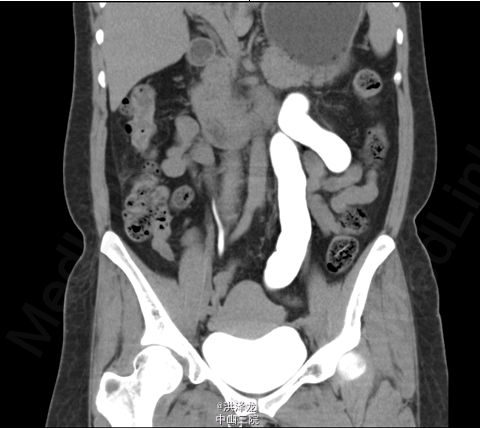

患者,女性,46岁。下腹胀痛半年。患者于6月前无明显诱因出现下腹部闷痛不适,无尿频、尿急、尿痛,无排尿困难,无血尿、脓尿,在当地医院行B超检查提示:左侧巨输尿管伴左肾 积液。现为进一步诊治收入我科。

双肾区无红肿、隆起,左肾区叩击痛(-),右肾区叩击痛(-),左侧肋脊点、肋腰点压痛(-),右侧肋脊点、肋腰点压痛(-)。腹平软,左侧输尿管走行区压痛(-),右侧输尿管走行区压痛(-),膀胱区无膨隆,压痛阴性。 CTU检查提示:左输尿管中段约平S1水平管腔稍变窄,其以下输尿管通畅,并进入膀胱内,其以上输尿管迂曲、扩张,扩张程度大致同前; 肾功能检查:左肾灌注正常,总体功能基本正常,左上尿路机械性梗阻

诊断:左侧巨输尿管。经术前准备后,行腹腔镜下左侧输尿管再植术,手术顺利,术后恢复较好。